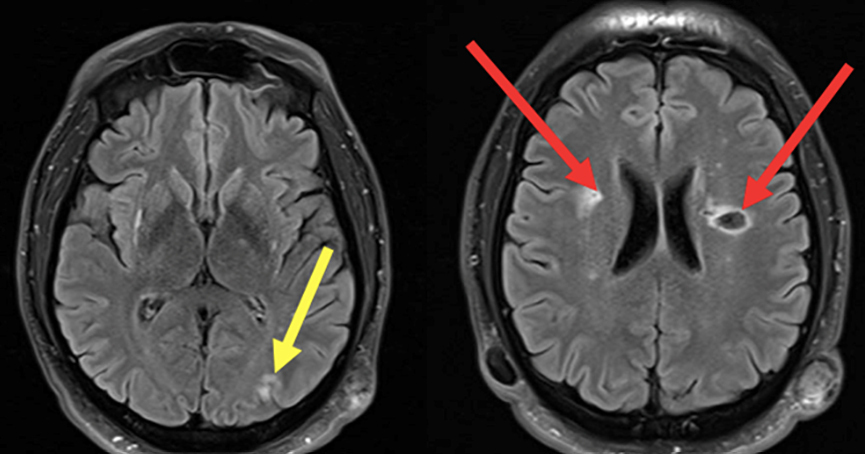

Le type d’hémianopsie est très important car il permet de localiser une atteinte neurologique, en connaissant le trajet des voies optiques.

Figure d’après le Collège des enseignants de neurologie (CEN). Altération aiguë de la vision.

Cette question supposait d’avoir bien en tête le schéma des voies optiques, et d’avoir des repères sur les principaux territoires vasculaires cérébraux et l’atteinte clinique associée. Il bien mentionné par le CEN que l’hémianopsie latérale homonyme gauche peut se voir dans un AVC sylvien superficiel droit.

Tableau d’après le Collège des enseignants de neurologie. Altération aiguë de la vision.